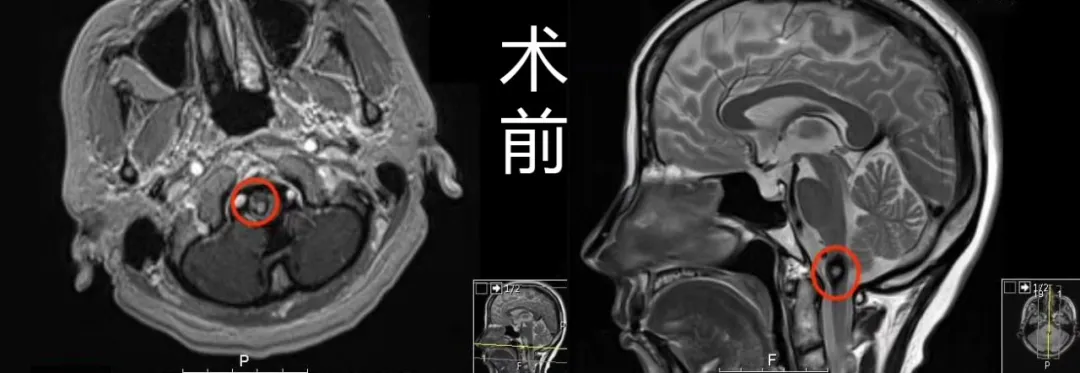

(术前术后MR对比)

术前MR显示:延颈髓偏右侧见一直径约1cm占位性病变,周围见环状含铁血黄素低信号影环绕,提示海绵状血管瘤。